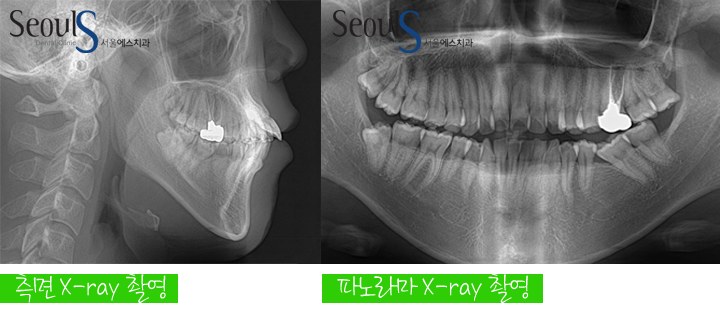

교정 진단

돌출과 삐뚠 치열을 교정 치료로 개선 하기로 계획했고

측면 X-ray 촬영, 파노라마 X-ray 촬영, 진단 모형 제작 및 분석 후 컴퓨터 교정프로그램에 입력해 진단했습니다

진단 내용

삐뚠 치열과 돌출을 해결하기 위해  공간이 필요한데

공간이 매우 부족한 상태였기 때문에 작은 어금니를 발치해 공간을 만들어

교정 치료를 진행하기로 계획했습니다